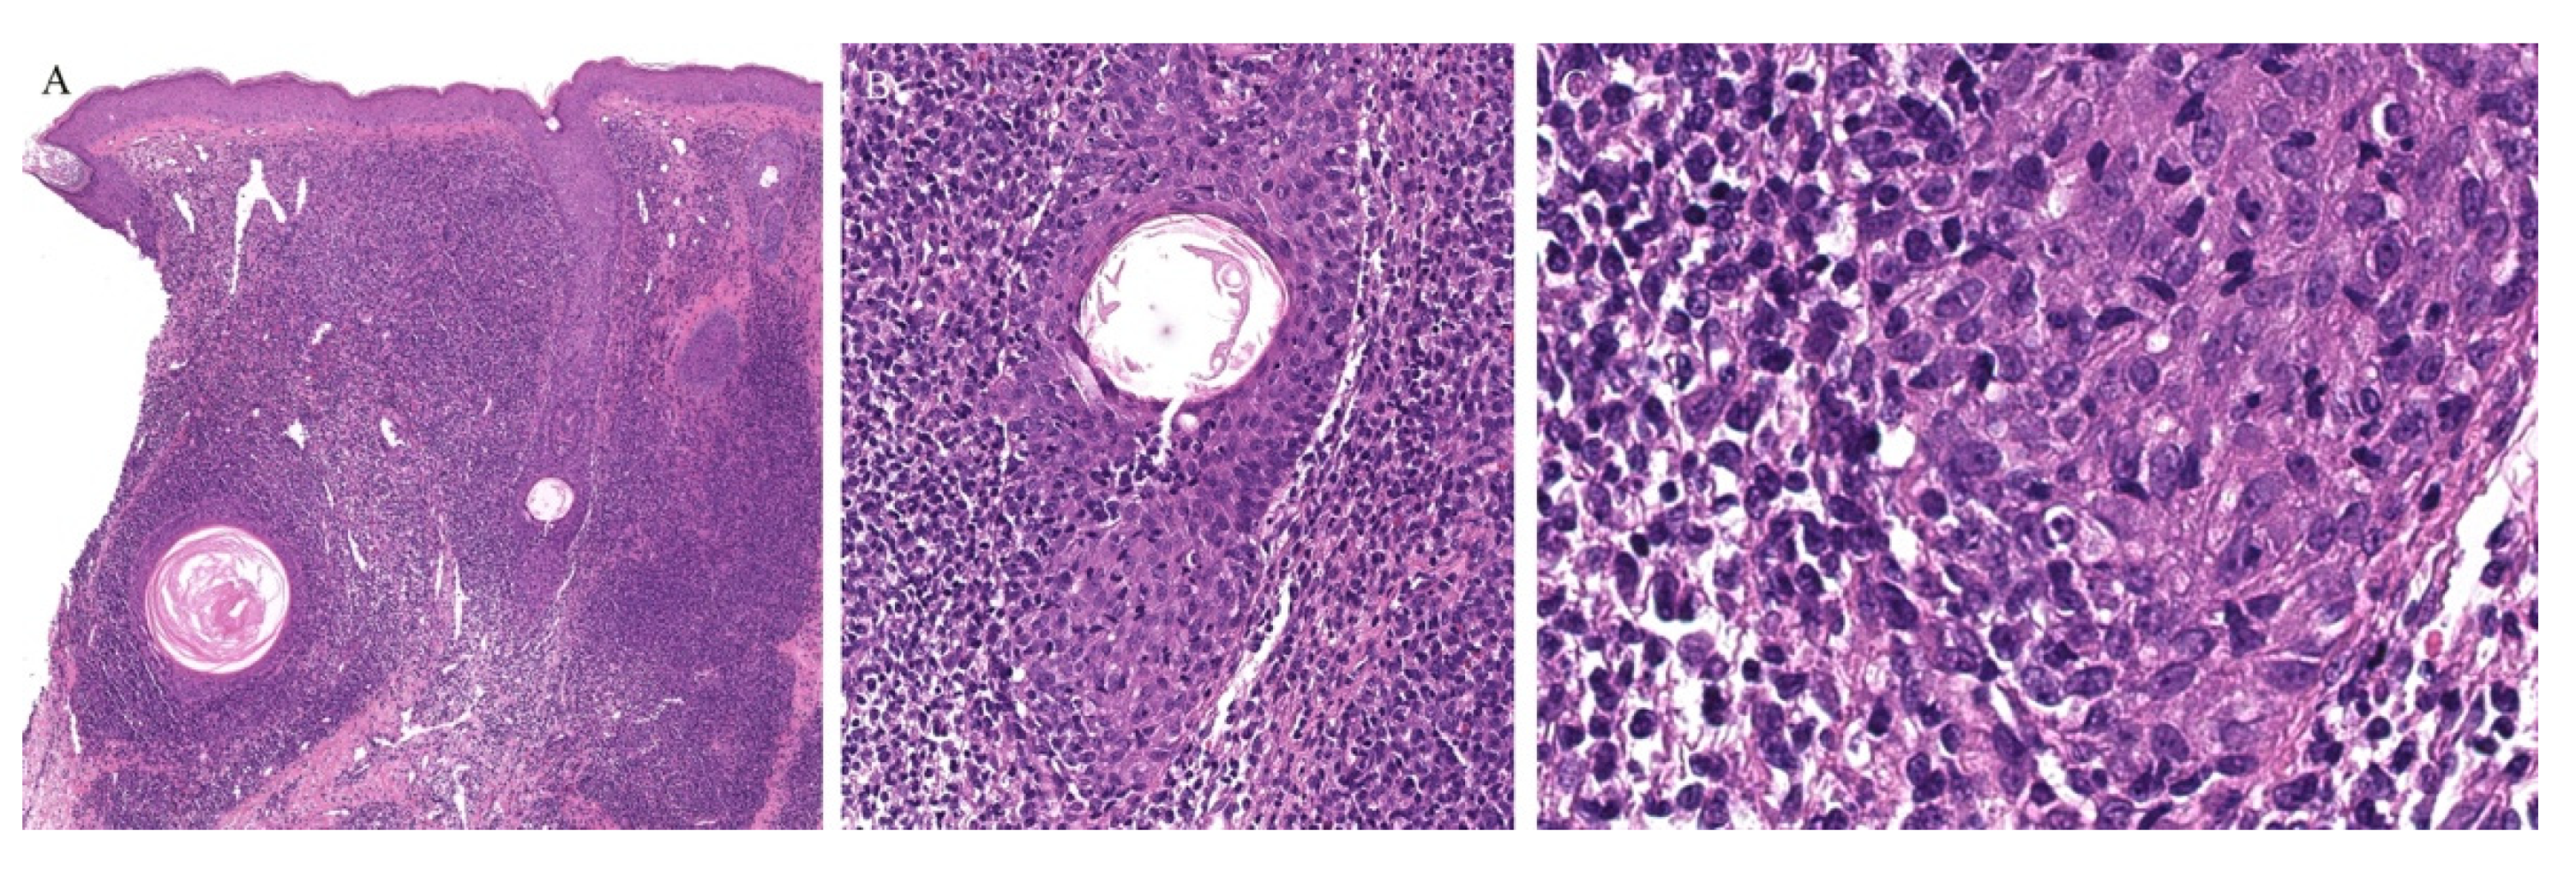

Lichen planus is the prototype lichenoid dermatitis characterized by a self-limiting eruption of pruritic flat-topped violaceous papules. On histopathology, hyperkeratosis, hypergranulosis, irregular acanthosis, and subepidermal clefts known as Max Joseph spaces are observed. A band-like lymphohistiocytic infiltrate is also seen. Distinct adnexotropic variants of lichen planus have been described (Figure 1). These include follicular lichen planus, lichen planus follicularis tumidus, and syringotropic lichen planus.

Lichen planopilaris, or follicular lichen planus, is a distinct variant of lichen planus whereby inflammation is seen around the hair follicle both clinically and histologically (Figure 1). Clinically, this presents with perifollicular erythema, follicular keratotic plugs, and a scarring alopecia [1,2].

Lichen planus follicularis tumidus (LPFT) is another distinct adnexotropic variant of lichen planus. Clinically, it is characterized by the presence of typical lichen planus lesions with the addition of comedo-like lesions and keratin-filled cysts, most commonly located in the retroauricular area. Most patients have classical lichen planus lesions on other parts of the body. On histopathology, the typical features of lichen planus are seen along with the involvement of the hair follicle. Follicular hyperkeratosis is observed and the follicular infundibulum is cystic and dilated. The follicular infundibulum is also surrounded by a lichenoid infiltrate [3]. Recognizing this entity is important as the differential diagnosis includes cutaneous lupus erythematosus (LE) with cysts and comedones and follicular mycosis fungoides (MF). Cutaneous LE is characterized by increased mucin deposition not seen in LPFT, while the presence of epidermotropism and an infiltrate of atypical lymphocytes is noted in follicular MF and not in LPFT [4].

Figure 1. (AC) Lichen planus with follicular involvement.